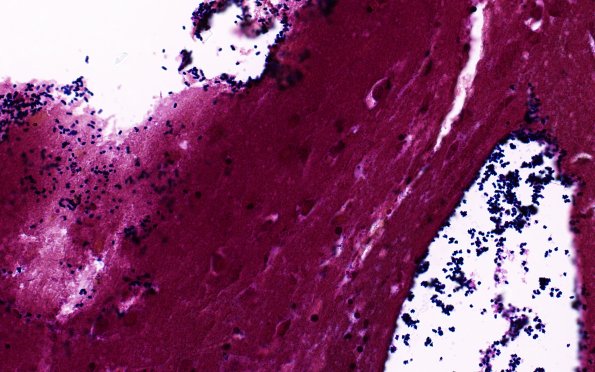

34C2B Swiss Cheese Brain (Case 12) Gram 40X 7

Bacteria are found in the vasculature and at the margins of the cysts. (Gram)